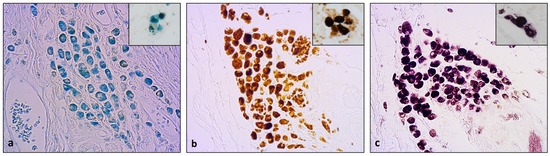

Macrophages are among the main actors in cancer immunoediting, with several functions, including recycling iron and packaging it in hemosiderin. Even though TAMs are widely studied in breast cancer and canine mammary tumors, hemosiderin-laden macrophages (HLMs) have not received as much attention. Considering [...] Read more.

Macrophages are among the main actors in cancer immunoediting, with several functions, including recycling iron and packaging it in hemosiderin. Even though TAMs are widely studied in breast cancer and canine mammary tumors, hemosiderin-laden macrophages (HLMs) have not received as much attention. Considering the growing interest in iron metabolism in cancer, this study aims to evaluate the presence of HLMs in canine mammary tumors. Fifty cases of canine mammary carcinomas presenting aggregates of pigmented macrophages were chosen. Prussian blue and Meguro staining were performed to assess the presence of iron. Immunohistochemistry was carried out to try to identify macrophagic phenotypes and hypothesize their role. Evaluation of the H&E sections showed that pigmented macrophages were variously localized in peritumoral and stromal areas. These pigmented cells were variably stained with Prussian blue and reacted strongly with DAB in the Meguro staining method, thus confirming the presence of iron within them. In their immunohistochemistry, the HLMs were negative for the MAC387 but positive for CD 204 and VEGF. Considering their positivity for CD 204, HLMs could be M2 macrophages that supply iron to both the neoplastic cells and the tumor inflammatory microenvironment, promoting angiogenesis and protecting cancer cells from hypoxia. Full article